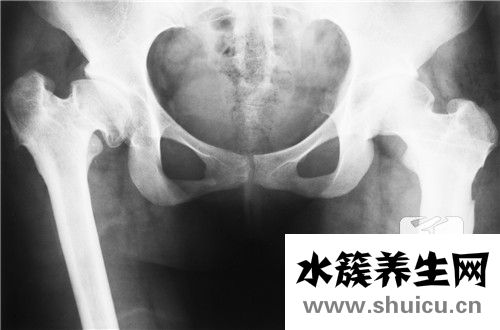

足跟骨刺即足跟骨質增生,其病癥是足根壓疼,行走時腳后跟害怕用勁,有石硌,扎針的覺得,活動開后,病癥緩解,踝關節骨折位置長骨刺,常見于中老年.一樣會出現腫脹病癥,且腳后跟,腳底板會出現痛感或者麻木感,乃至會造成沒法踏地走動的狀況,一早醒來站起時這類疼痛特別是在顯著,但是,徒步一段時間后,這類疼痛反倒會緩解.一般是早上重,中午輕.